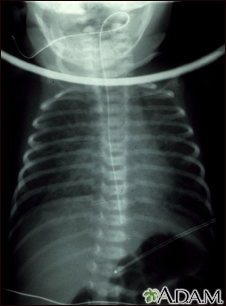

Totally anomalous pulmonary venous return - x-rayBackTotally anomalous pulmonary venous return - x-rayTotally anomalous pulmonary venous return (TAPVR) is a form of congenital heart disease. This x-ray shows an enlarged heart, a large liver, and increased size of the lung blood vessels (pulmonary vascularity). E-mail FormEmail ResultsName:Email address:Recipients Name:Recipients address:Message: